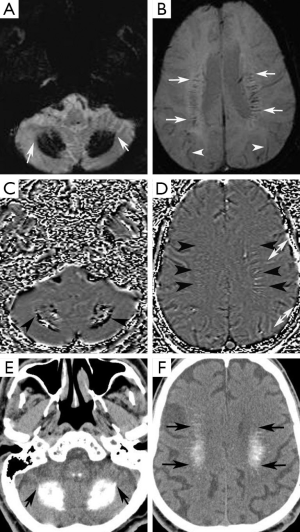

A 74-year-old man presented at our neurology outpatient clinic with headache, progressive short-term memory deficit for 1 year, and weakness of the upper and lower extremities with tremor. Neurological examination with standard neuropsychological tests showed slight cognitive deficit, characterized by memory impairment. Cranial MRI revealed diffuse symmetrical hyperintense signal in the bilateral basal ganglia, dentate nuclei, and also involving the periventricular white matter and centrum semiovale bilaterally on T2-weighted and FLAIR images (Figure 1A,B). T1-weighted images showed mild hyperintense signal changes in the dentate nuclei and minimal hyperintensity in the centrum semiovale (Figure 1C,D). In addition, cerebral and cerebellar atrophy was noted (Figure 1). These signal changes were hypointense on SWI minimal intensity projection (minIP) and phase images, consistent with calcification (Figure 2A-D). Brain CT imaging confirmed calcifications. (Figure 2E,F). Electroencephalogram (EEG) was normal. Laboratory data including metabolic tests which were performed to investigate calcium deposition disorders (including Ca/P, parathormone hormone) were unremarkable. On the basis of laboratory test results, neuroimaging findings, and clinical data, FD was diagnosed.